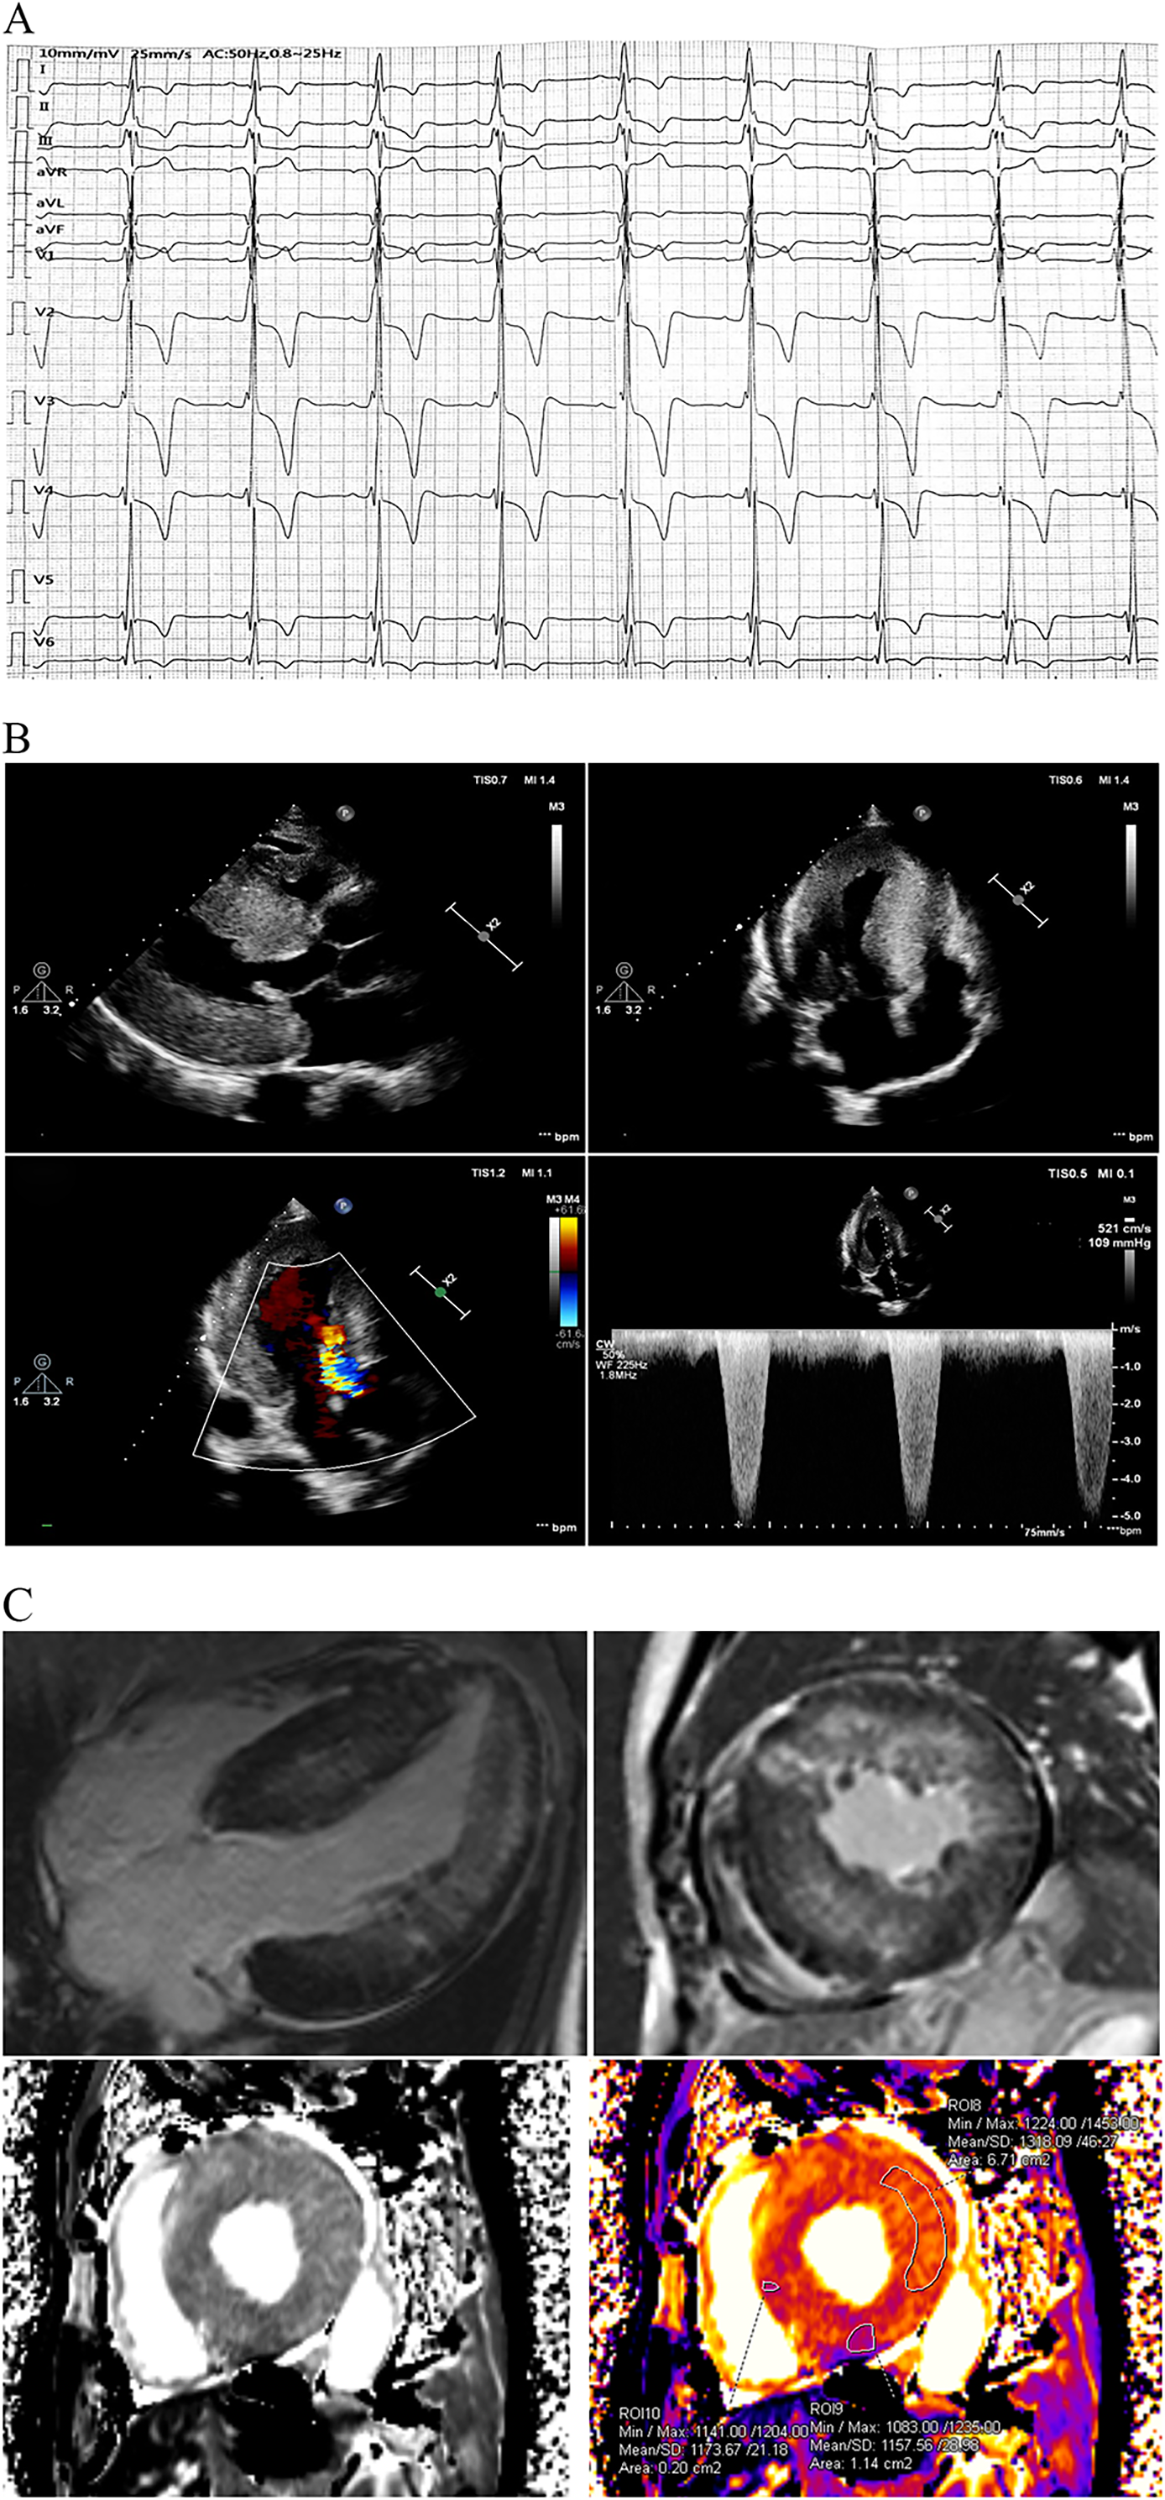

The proband sought medical advice for mild chest discomfort in 2019. Physical examination revealed a grade 4/6 systolic ejection murmur in the third and fourth left intercostal spaces upon cardiac auscultation. The electrocardiogram showed inverted T-waves and abnormal QRS complexes in nearly all leads (Figure 1A). Transthoracic echocardiography (TTE) revealed severe concentric left ventricular hypertrophy consistent with obstructive hypertrophic cardiomyopathy (Figure 1B). The diastolic interventricular septal thickness measured 27 mm, while the maximum thickness at the basal segment was 30 mm. The diastolic left ventricular posterior wall thickness was 24 mm. Systolic anterior motion of the mitral valve was observed, with a left ventricular outflow tract gradient of 109 mmHg measured at rest. Further confirmation of obstructive hypertrophic cardiomyopathy was obtained via cardiac magnetic resonance imaging (CMR). Late gadolinium enhancement revealed diffuse fibrosis of left ventricle without reduction of T1 mapping (Figure 1C). Coronary angiography was performed due to suspected coronary artery disease, revealing mild stenosis of approximately 20% in the proximal left anterior descending artery.

Figure 1

Clinical data at first medical contact. (A) The ECG exhibited inverted T-waves with abnormal QRS complexes in nearly all leads, indicating left ventricular hypertrophy. The PR interval measured 202 ms, suggesting that the patient was in an advanced stage of the disease. (B) TTE revealed severe concentric left ventricular hypertrophy consistent with obstructive hypertrophic cardiomyopathy, with a left ventricular outflow tract gradient of 109 mmHg at rest. (C) CMR using late gadolinium enhancement demonstrated diffuse fibrosis of the left ventricle. Notably, T1 mapping on CMR was not reduced, which contrasts with previous reports. ECG, electrocardiogram; FD, Fabry disease; TTE, transthoracic echocardiography; CMR, cardiac magnetic resonance imaging.